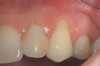

Fig 1. Miller Class I recession on tooth No. 11 (Fig 1) treated with tuberosity CTG (Fig 2). Note this CTG (which is the tuberosity CTG from Fig 5) was placed before the practitioner developed thinning techniques, so a keloid-like appearance was observed even 1 year after grafting.

Figure 1

Fig 2. Miller Class I recession on tooth No. 11 (Fig 1) treated with tuberosity CTG (Fig 2). Note this CTG (which is the tuberosity CTG from Fig 5) was placed before the practitioner developed thinning techniques, so a keloid-like appearance was observed even 1 year after grafting.

A complication in using CT from the tuberosity reported in the literature is a tendency for clinicians to harvest tissue that is too thick.12 This can result in a keloid-like appearance similar to what may occur with an EPG. This excess thickness can be unesthetic (Figure 1 and Figure 2) and subsequently require a gingivoplasty to remove the superfluous tissue.12 This problem may perhaps be alleviated with proper thinning of the graft prior to insertion into the recipient area.